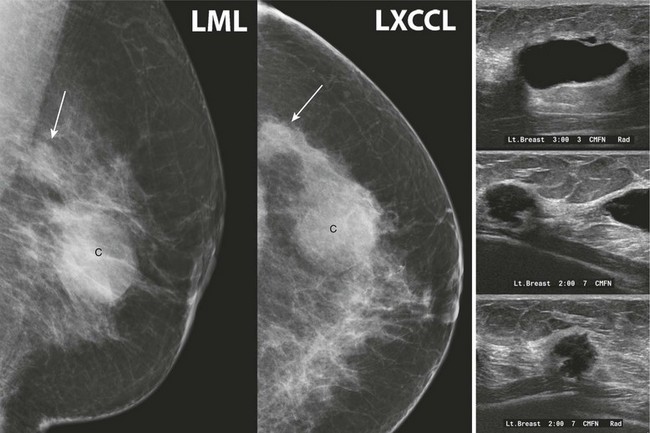

CASE 8-5. Screening mammogram of a 49-year-old woman with a comparison study from 1 year prior. A left breast cyst (C) was diagnosed by previous US. Can the rule of multiplicity be applied? What do you recommend?

CASE 8-5. There are two masses in the left breast, including the previously documented cyst (C), which has obscured margins. The more posterior mass is excluded from the screening CC view but is confirmed on the exaggerated craniocaudal lateral (XCCL) and mediolateral views (arrows). It has enlarged since the previous mammogram.

The rule of multiplicity should not be applied. The masses are unilateral. The posterior left breast mass has suspicious features (irregular shape, indistinct margins) and has clearly enlarged. There is a dense left axillary lymph node. US shows the known cyst and an adjacent, irregular hypoechoic mass, which was biopsied. Diagnosis: IDC grade 2.